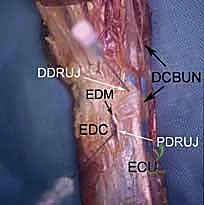

Dorsal Distal Radioulnar Joint (DRUJ) Portals

These portals offer direct access to the DRUJ for assessing its articular cartilage and ligaments.

1. The Dorsal Radioulnar Joint Portal (Proximal and Distal)

- Location: Lies between the ECU and the EDM tendons. There can be a proximal (PDRUJ) and a distal (DDRUJ) portal.

- Anatomy: The interval between the fifth (EDM) and sixth (ECU) extensor compartments.

- Neurovascular Risks: Transverse branches of the dorsal cutaneous branch of the ulnar nerve are the only sensory nerves in proximity, typically at a mean of 17.5 mm distally (range 10–20 mm) from the portal. Careful dissection is still advised.

- Function: Used in concert with the volar distal radioulnar portal to fully assess the articular cartilage of the ulnar head and sigmoid notch, and for instrumentation within the DRUJ.

2. The 4-5 Portal

- Location: Situated between the fourth and fifth dorsal extensor compartments.

- Anatomy:

- Fourth Compartment: Extensor digitorum communis (EDC) tendons.

- Fifth Compartment: Contains the extensor digiti minimi (EDM) tendon.

- Neurovascular Risks: Similar to the 3-4 portal, generally safe, but transverse branches of the dorsal cutaneous branch of the ulnar nerve can be in proximity. Again, blunt dissection is key.

- Function: A crucial viewing portal for the ulnocarpal joint and for introducing instruments to address ulnar-sided pathology, particularly TFCC tears.